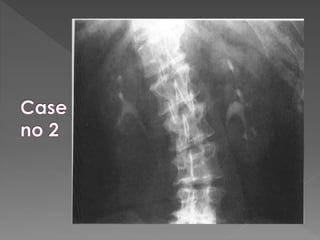

X ray films 1)Pre contrast 2) 5 mins 3) 25 mins 4) Post void